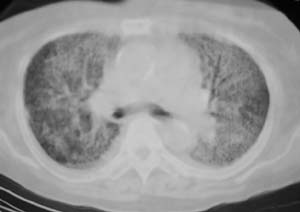

以下是引用liaizhi在2007-7-6 0:05:00的发言:[br]双肺纹理膜糊,沿纹理走行有班点状高密度影。考虑心衰并肺水肿。

以下是引用andymaomao在2007-7-5 22:23:00的发言:[br]双上肺明显,考虑心衰并肺水肿,双侧胸腔少量积液!另不除外肺泡蛋白沉着症及肺泡ca可能。[br]联想机制——心脏病(代偿期)--肺部淤血--后可能并感染致病情加重--抗炎治疗好转,但肺淤血严重,心功能失代偿--心衰而死亡!

以下是引用拾荒者在2007-7-6 13:06:00的发言:[br]支持:心衰,肺水肿及ards